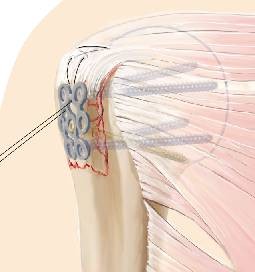

Darstellung der Tuberculum-majus-Fraktur über anterolateralen Deltoideus-Split. Reposition der Fraktur und passagere Retention durch Kirschner-Draht oder Kugelspieß oder Anschlingen der Supraspinatussehne und Retention nach distal. Manuelles Vorbiegen und Auflegen der Bamberger Platte und Fixierung mit konventionellen und/oder winkelstabilen Schrauben. Optionales Fixieren der Rotatorenmanschette an der Platte. Genaue Kontrolle der Implantatlage mit Bildverstärker zur Vermeidung einer unzureichenden Distalisierung des Tuberculum majus.

Exposure of the fracture of the greater tuberosity by an anterolateral approach. Open reduction and temporary retention with a Kirschner wire or a “Kugelspieß” or reinforcement of the supraspinatus tendon and distal retention. Bending and positioning of the Bamberg plate and fixation by conventional or locking screws. Optional fixation of the rotator cuff to the plate. Exact monitoring of the implant position using the image intensifier to avoid inadequate distalization of the greater tuberosity.

Abb. 4

Abb. 5